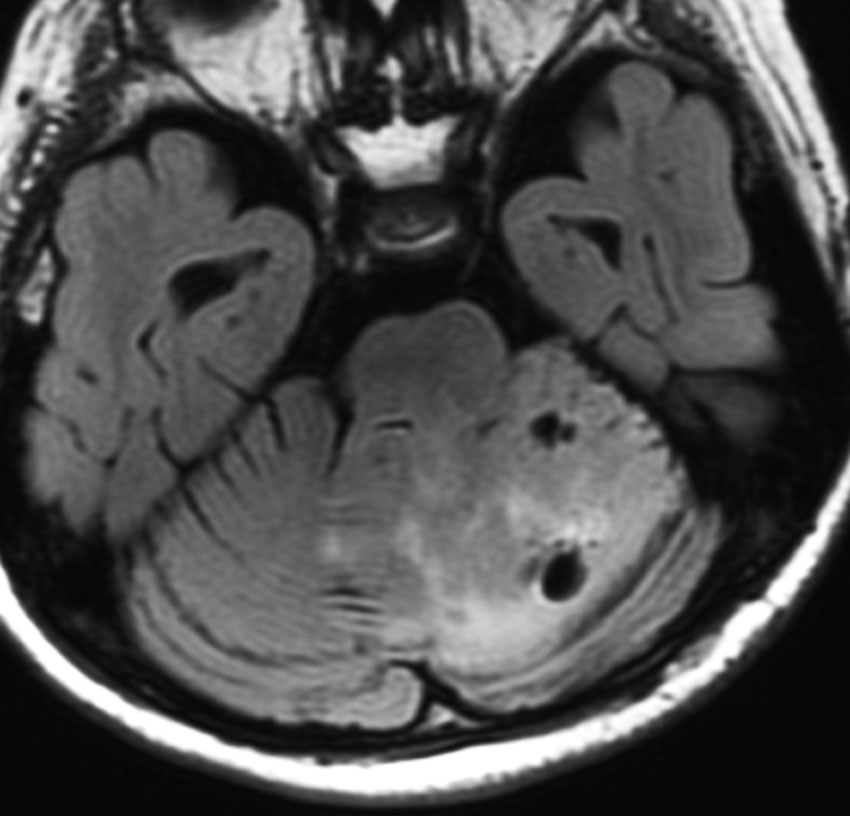

上にお見せした例の8年後の画像です。腫瘍は8年間で全く大きくなりませんでした。

15年後,17歳の時の画像です。全く変化がないかごくわずかに退縮しているかもしれません。自転車にも乗れます,ちょっと走ることが遅い普通の高校生です。